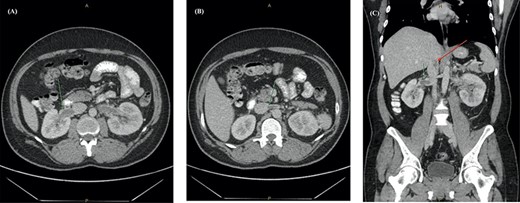

Post-discharge, he continued to experience worsening abdominal pain prompting further re-presentation. An abdominal CT with contrast showed bilateral RVT with infra-hepatic extension into the inferior vena cava (IVC) (Fig. 2). The patient was admitted under the vascular unit for a comprehensive workup.

Abdominal CT with contrast showing (A) an enlarged right renal vein with a filling defect, (B) left renal vein distension and filling defect with (C) extension into the lower intra-hepatic inferior vena cava (red arrow).